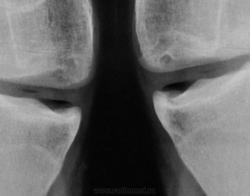

Направлен был традиционно из военкомата для рентгенографии стоп и позвоночника. Но лаборант заметил, что "клиент" полностью, в положении лёжа, ноги в коленных суставах не разгибает. Решили дополнительно "снять" коленные суставы...

Дисплазия это...

Похоже+дольчатое строение надколенников.

Кажущаяся нестабильность надколенников (их латерализация) связана с укладкой, или же это одно из проявлений дисплазии?

Как на ваш взгляд - это "вакуум-феномен"?

ДА! И еще какой!

Можно было бы обозвать его - "диспластическим", в такой ситуации встречаюсь впервые))))

МРТ полностью подверждает дисплазию

Эпифизарная дисплазия.